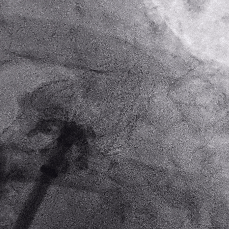

术中封堵器展开过程

鞘管定位

展开过程

Lefort封堵器展开后DSA评估和调整

肝位即刻造影,位置合适,上下缘无造影剂漏

牵拉时造影,有明显回弹,牵拉后位置无移动

封堵器未肩部

锚定区压缩比10%